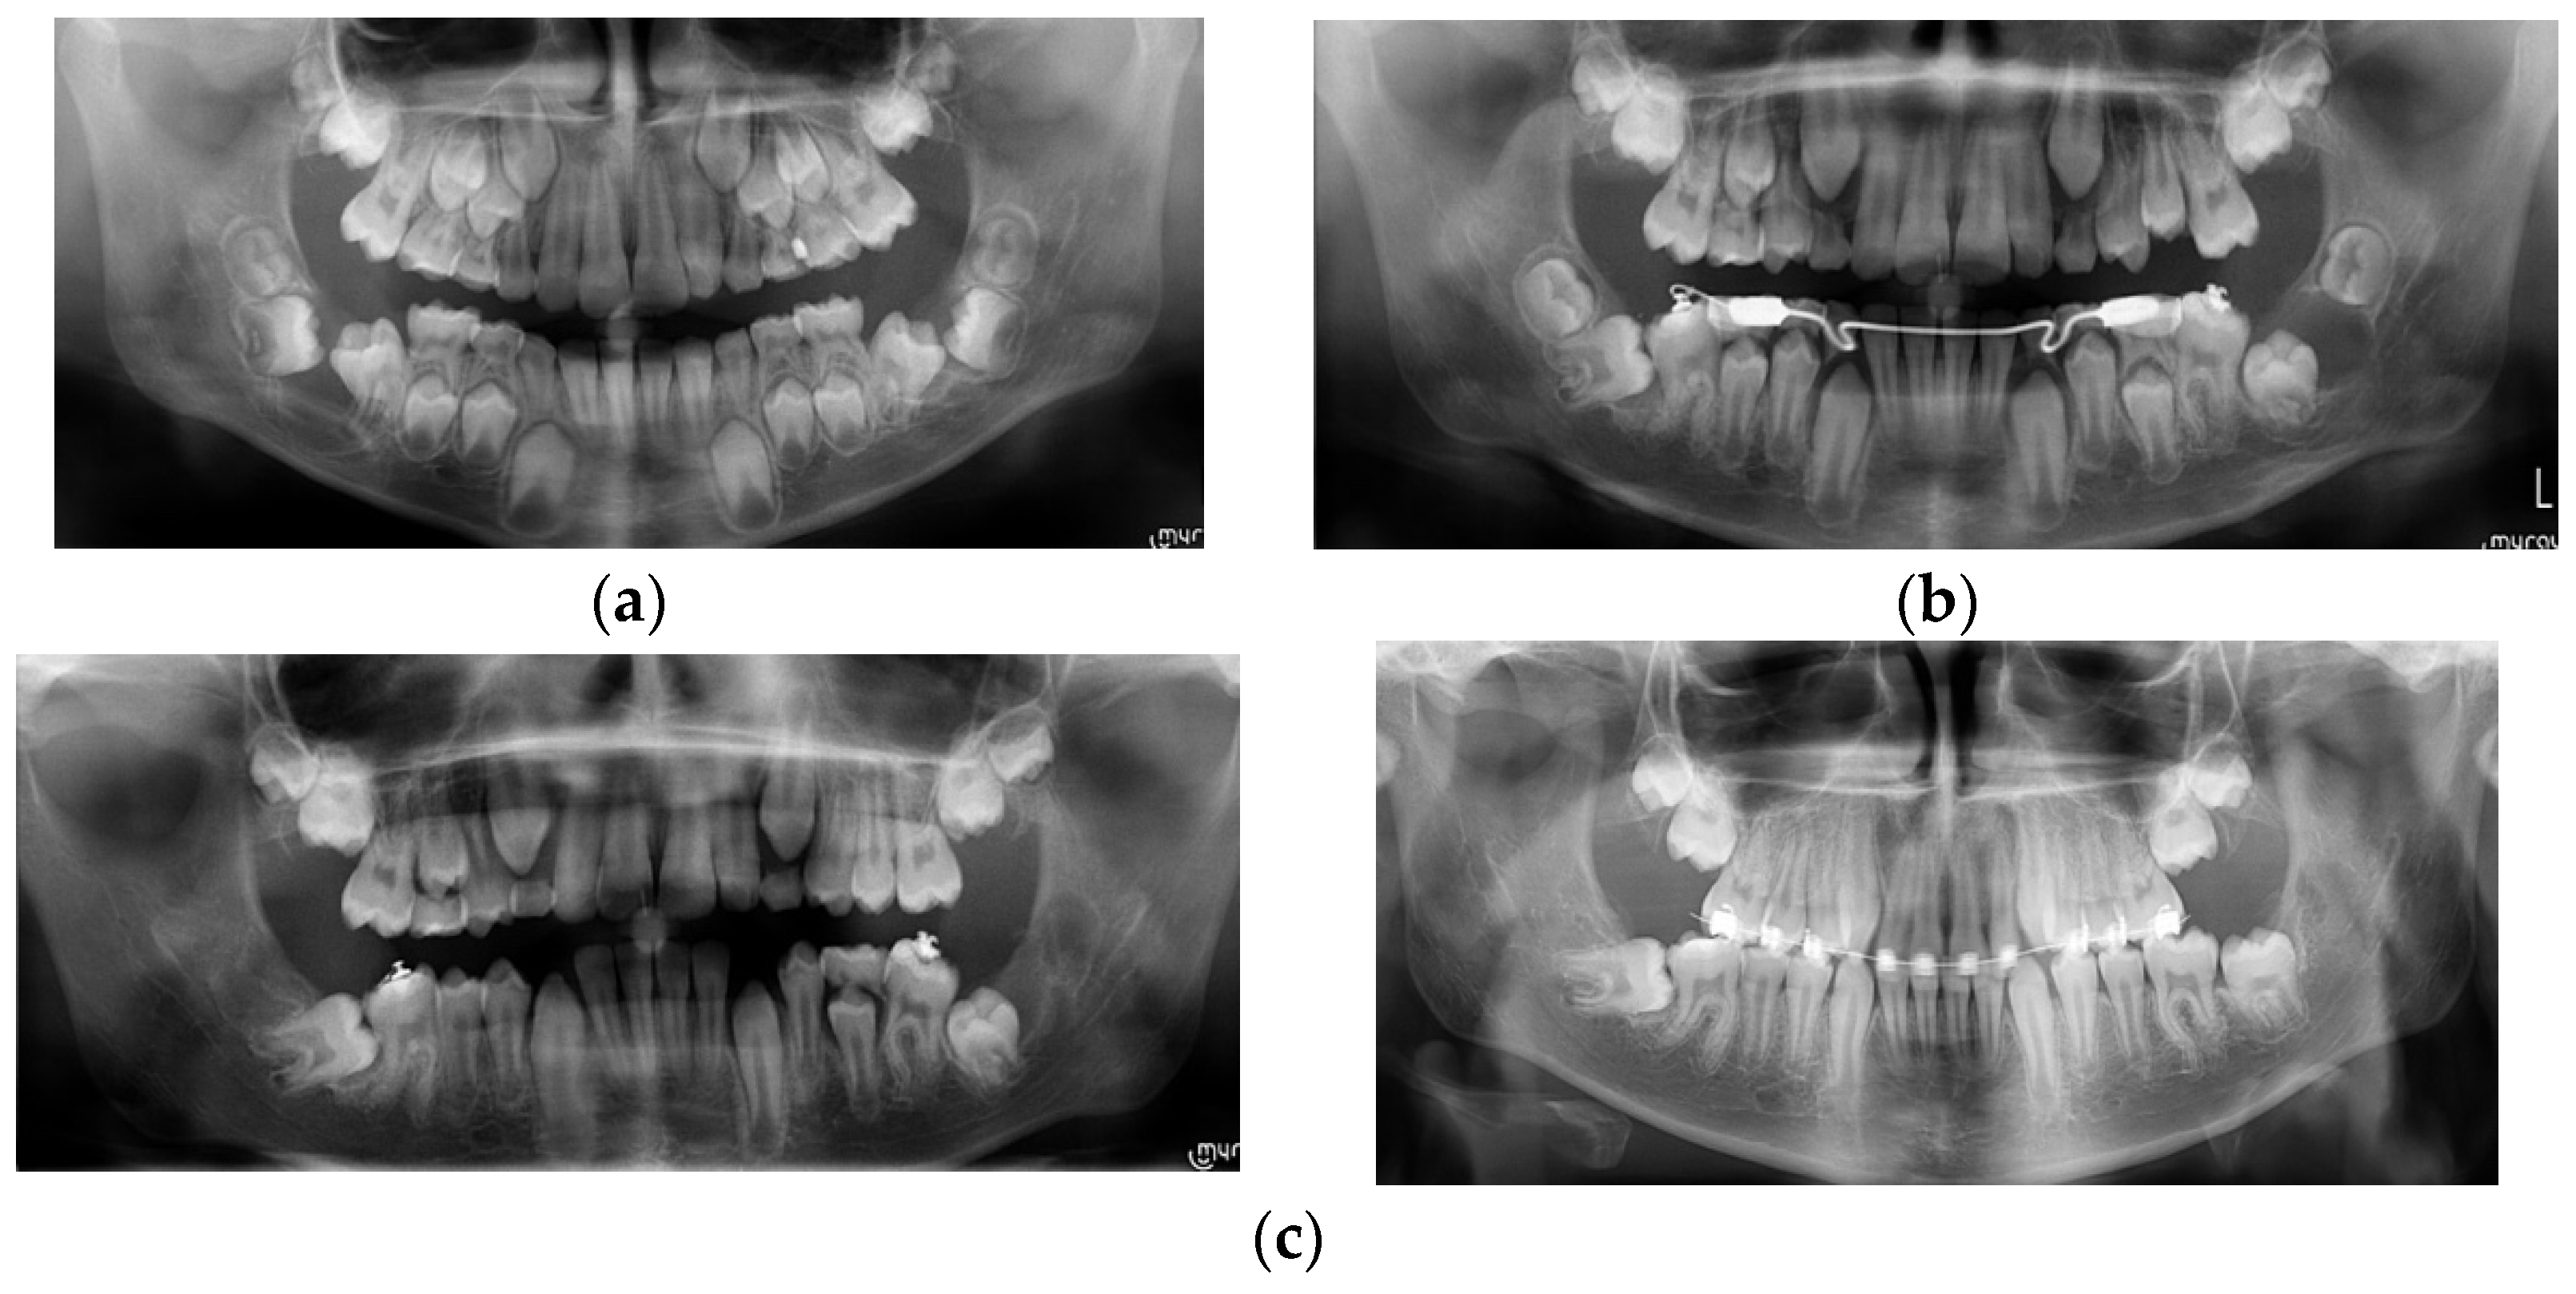

| Case Number | Summary of X-ray Findings |

| Case 4 |

|

| Case 5 |